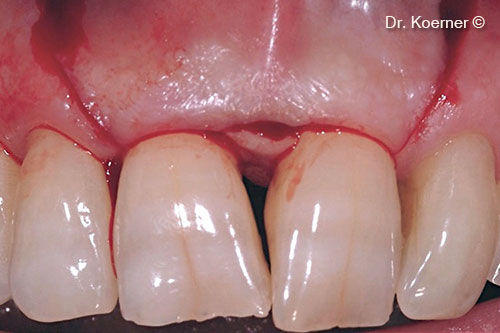

Clinical situation 6 months post-op

Clinical situation 10 years post-op

Final restoration with ceramic veneers 13-23